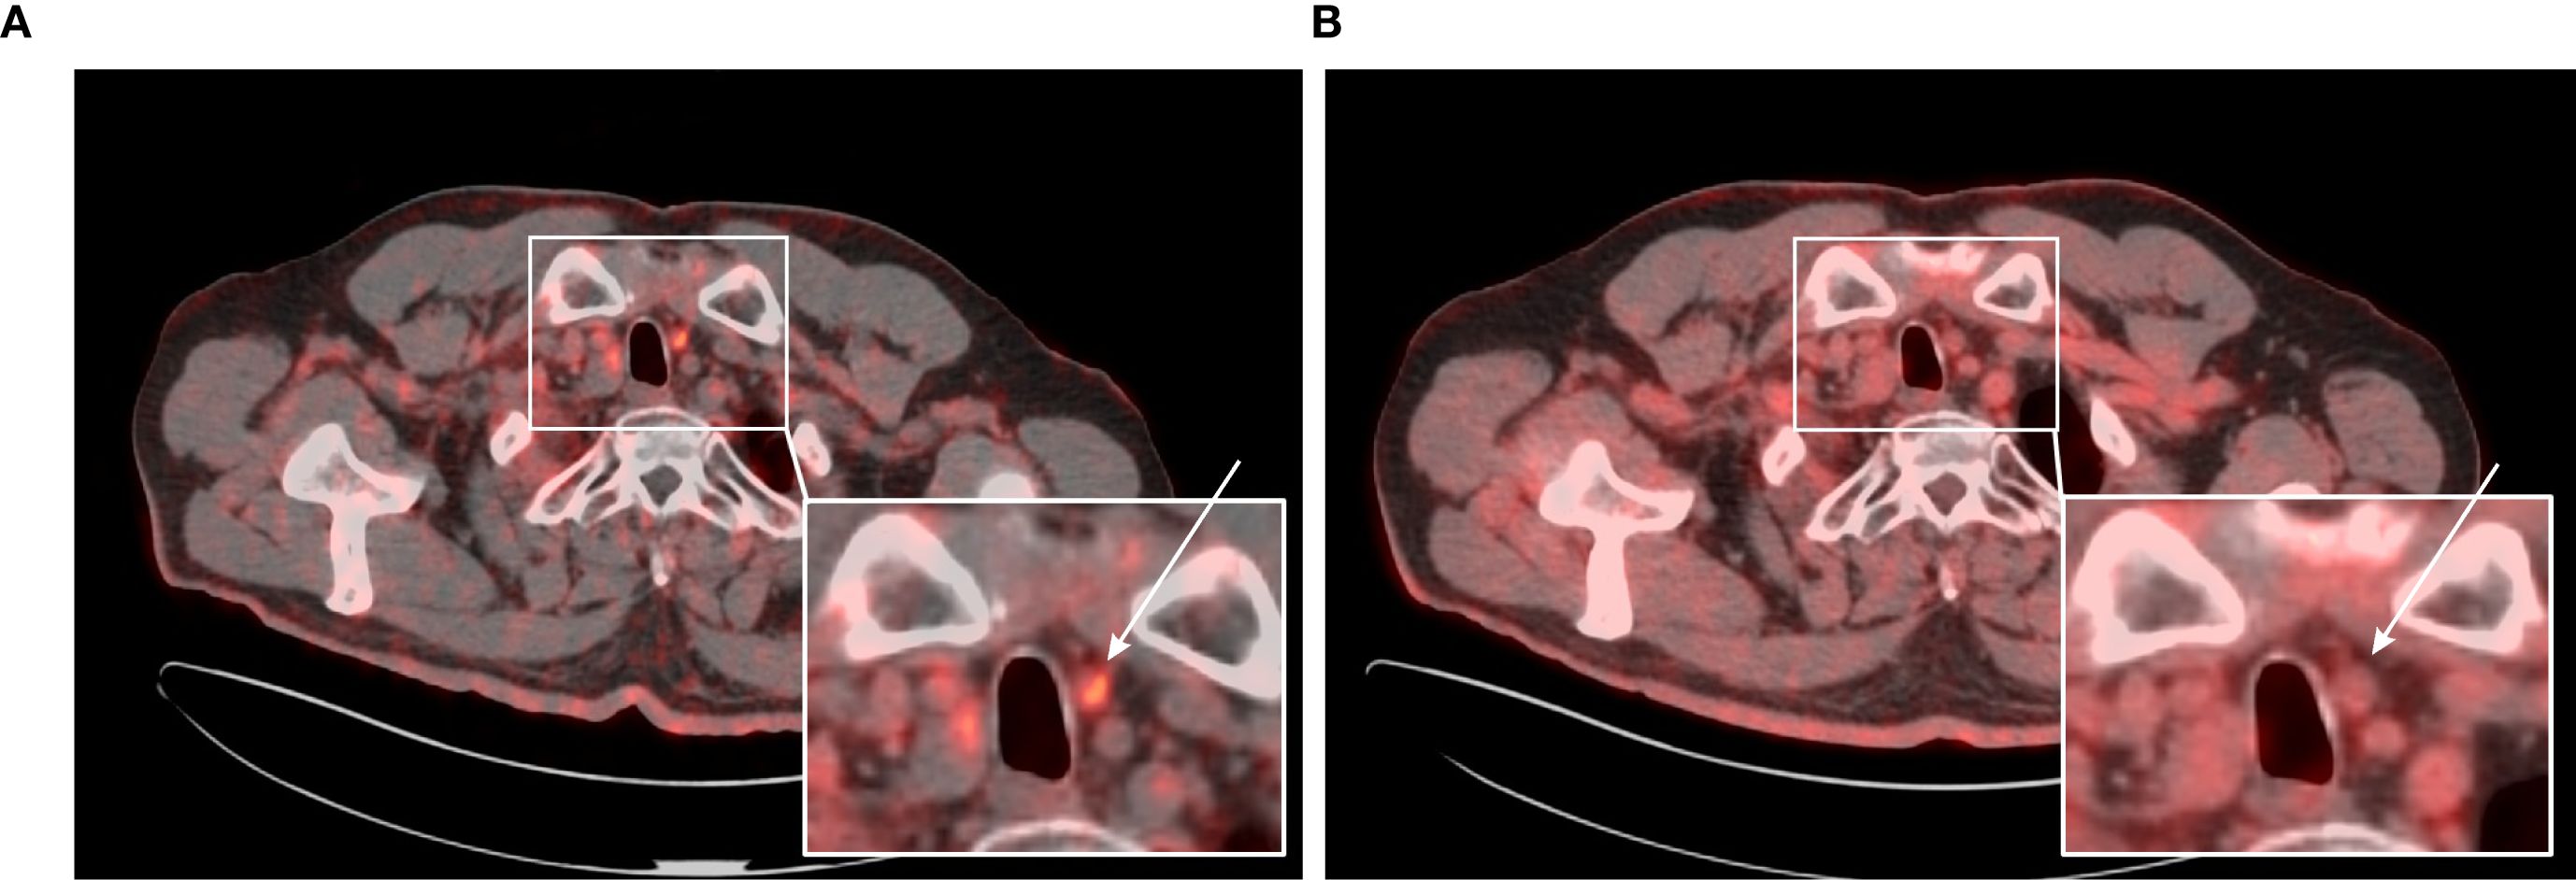

[68Ga]Ga-PSMA-11 PET/CT was positive in 5/12 patients – 3/3 patients with previously-identified structural lesions (a superior mediastinal mass, a metastatic cervical lymph node, and liver metastases; Figures 3–5) and 2/9 patients without previously known structural lesions. In both of these cases, [68Ga]Ga-PSMA-11 PET/CT revealed small lesions in the thyroidectomy bed, which could correspond to local recurrence or lymph nodes (one shown in Figure 6). The mean SUVmax, TBRBlood and TBRLiver values for detected lesions were 7.08 (range 2.74–12.37), 6.08 (range 3.19–9.82), and 2.23 (range 0.90–3.77), respectively.

Figure 6. (A) 65-year-old female with medullary thyroid carcinoma and recurrence in thyroidectomy bed. (A) Transaxial view of the fused [68Ga]Ga-PSMA-11 PET/CT scan. (B) Transaxial view of the fused [18F]FDG PET/CT scan. In the thyroid bed on the left side, a spherical soft tissue lesion measuring 9 × 8 mm demonstrates increased [68Ga]Ga-PSMA-11 uptake (SUVmax 2.74; TBRBlood 3.19) (white arrow). [18F]FDG PET/CT performed approximately 3 months later revealed that the same lesion, now measuring 11 × 10 mm, showed no evidence of increased [18F]FDG uptake (SUVmax 1.89; TBRBlood 0.82) (white arrow). Fine-needle aspiration biopsy confirmed the lesion as a metastasis of medullary thyroid carcinoma.